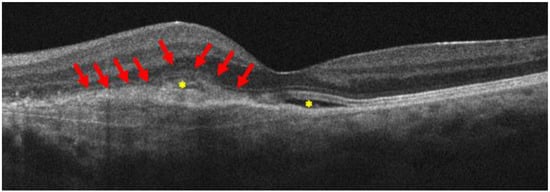

Three months later, she became pregnant and, in September 2023, eight days postpartum, having been induced with low-dose oxytocin (0.5 to 2 mU/min with incremental increases of 1 to 2 mU/min every 15 to 40 min) [36], she complained of blurred vision and metamorphopsia in her left eye. Her best corrected visual acuity was 20/200, and the OCT revealed the presence of hyporeflective intraretinal and subretinal fluid accumulation nearby the known retinal lesion (Figure 3).

Figure 3. B-scan OCT reveals an enlargement of the known retinal lesion, with a maximum retinal thickness of 433 microns, fuzzy borders, and subretinal hyperreflective material, which is a sign of progression of type 1 to type 2 MNV (red arrows), in the presence of intraretinal and subretinal fluid (yellow asterisks). All are imaging signs of MNV activation.